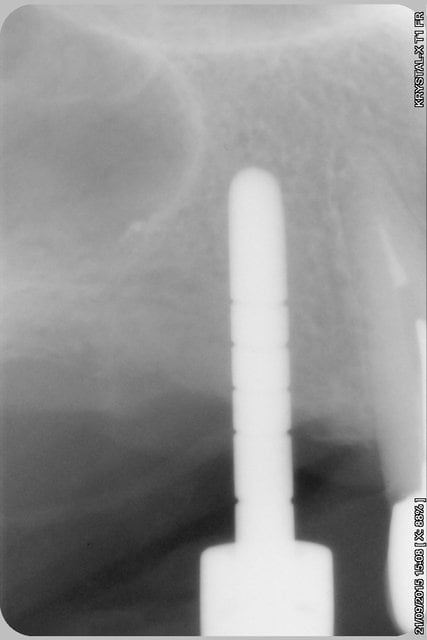

La rx avec bistouri en place sert à vérifier quoi?

la radio sert à vérifier la position de la lame 15, par rapport à la racine et au sinus, mais je ne suis pas sur que tu comprennes, que le bistouri est dans l'os, c'est l'instrument le plus fin et le moins traumatisant pour fendre l'os (je le préfère au piezzo et même au disque diamanté).